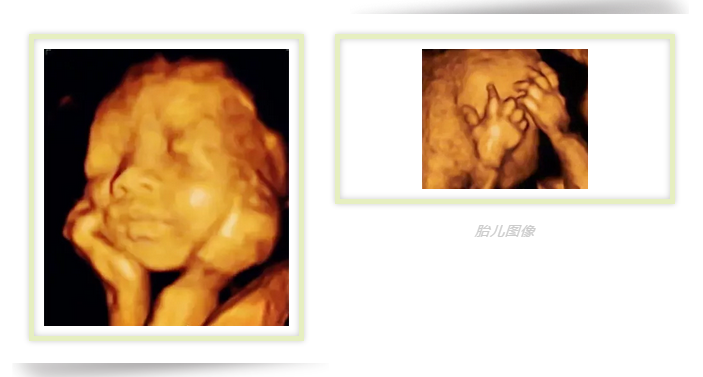

四维彩超的成像是动态的,医生能多方位、多角度、更准确的观察到宝宝的状态和生长发育情况。还能让宝宝和爸爸妈妈提前见面哦~!

为宝宝留下0岁纪念

四维彩超除了有超强的排畸功能之外,还有强大的拍摄功能,能抓捕胎儿的每个细小的动作。